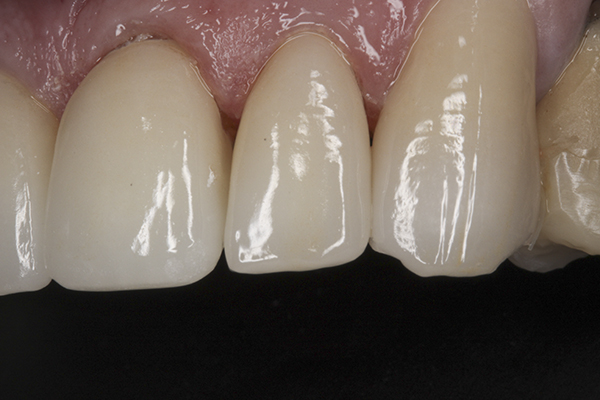

(38.) Postoperative right anterior, close-up view.

Figure 38

(39.) Postoperative anterior, close-up view.

Figure 39